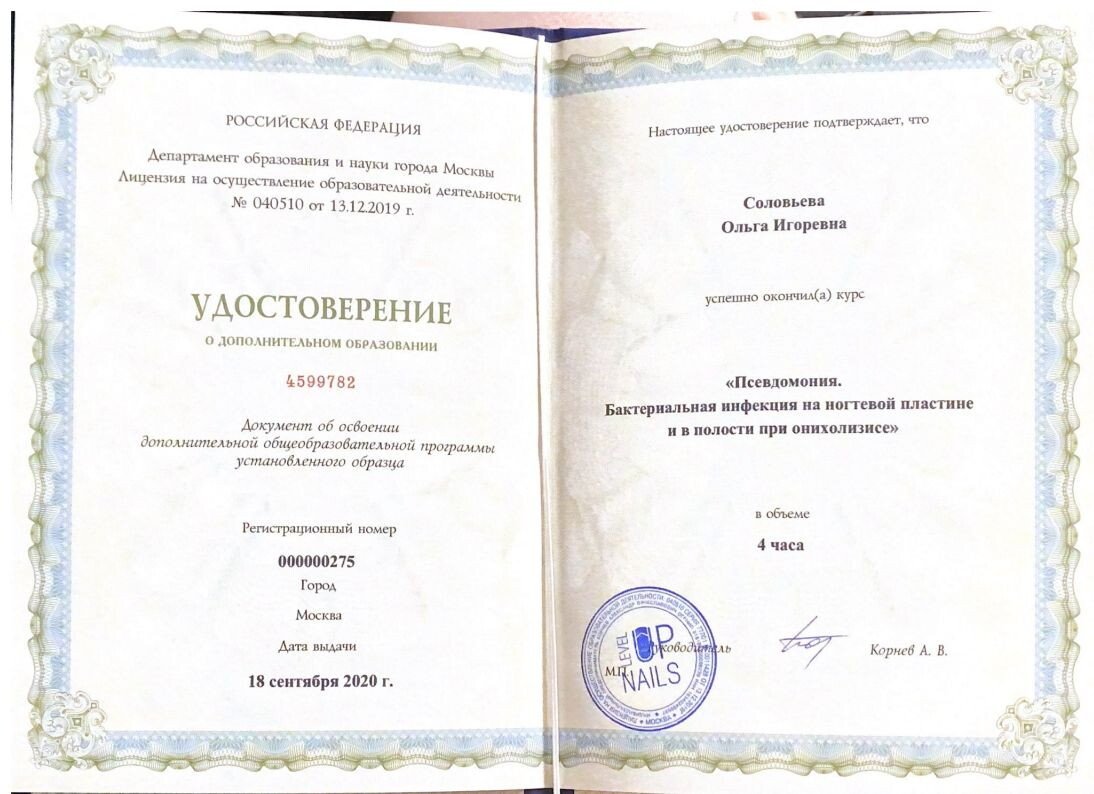

Знаю Ольгу Игоревну давно и уверена в ее профессионализме. Она постоянно учится и помогала мне с проблемами рук и ног, всегда справлялась сама, никого не перенаправляла. Она талантливый и умный доктор, профессионал.

Подолог Ольга Игоревна Соловьева отличный специалист, прекрасно разбирающийся в своей области. Раньше у меня наблюдалась грибковая инфекция на ногте, но сейчас она полностью исчезла, эффект очевиден. Для меня, как и для многих пациентов, главное добиться результата, я это получил. Советую обращаться именно к ней!

Ольга Игоревна — настоящий профессионал своего дела! Мне очень нравится, как она работает: всё делает качественно, внимательно, с душой. Сейчас прохожу лечение грибка ногтя — процесс, конечно, долгий, так как это же не быстрое дело, но я вижу результат и доверяю специалисту полностью. Ранее была в кожно-венерологическом диспансере, но здесь подход совсем другой, довольна подологической обработкой ногтей.